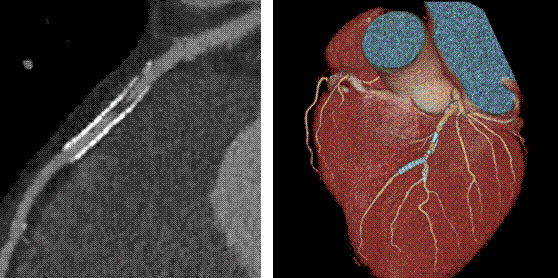

新技术介绍四:高心率冠脉成像、高清成像

此例为心率83~88bpm,冠状动脉成像优异

宝石能谱CT突破了以往64排CT冠脉扫描时对心率的苛刻要求,增加了患者的接受度,简化了冠脉CTA成像流程。

高清模式清晰显示支架术后再发斑块形成

高清模式突破了传统CT对支架内斑块观察的难点,能够提供冠脉支架内腔的高清图像。